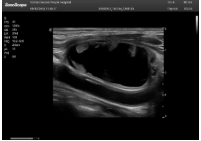

肝癌